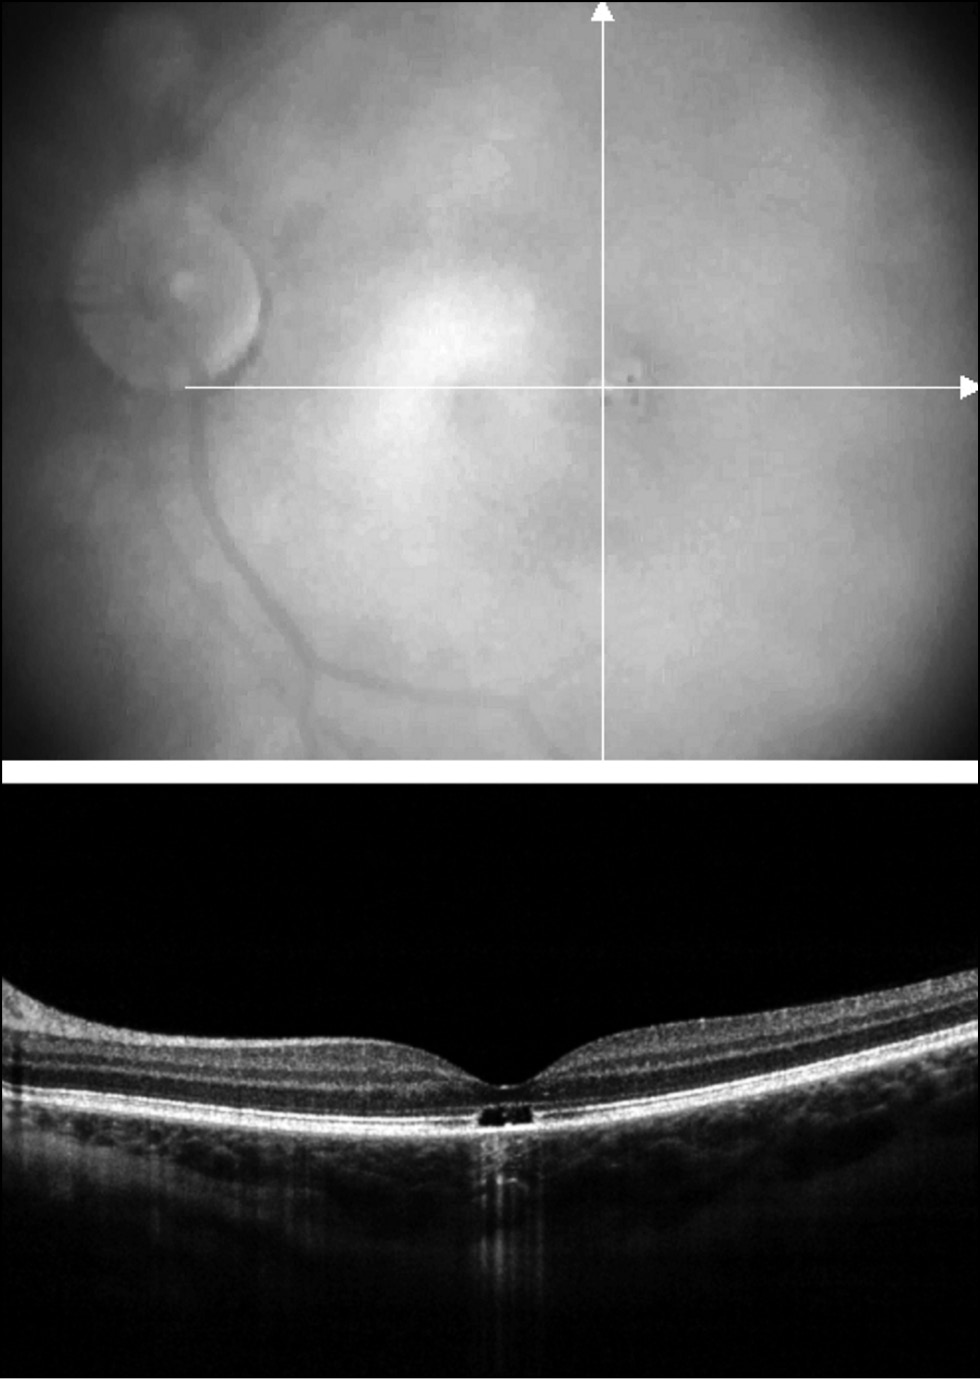

Случай 1. Девочка 12 лет обратилась в Центр с жалобами на снижение зрения левого глаза. Из анамнеза известно, что сниженное зрение выявили при профилактическом осмотре в школе. При тщательном сборе анамнеза выяснилось, что девочка 3 месяца назад играла лазерной указкой и светила ею в левый глаз. При объективном обследовании выявлено, что острота зрения правого глаза = 1,0 с коррекцией; левого глаза — 0,15, не корригируется. Оптические среды прозрачные. На глазном дне правого глаза патологии не выявлено. В левом глазу макулярный рефлекс был сглажен, в фовеа обнаружены мелкие очажки гипо- и гиперпигментации. По данным ОКТ, в левом глазу выявлено уменьшение толщины нейроэпителия в фовеа до 170 мкм (в правом глазу толщина нейроэпителия в фовеа составила 195 мкм), а также признаки локального разрушения пигментного эпителия и эллипсоидной зоны фоторецепторов (зона сочленений наружных/внутренних сегментов фоторецепторов) (рис. 1). При этом регистрировалась нормальная смешанная ЭРГ, а ритмическая и макулярная ЭРГ были субнормальными, что свидетельствовало о снижении электрогенеза центральных отделах сетчатки и преимущественном поражении колбочковой системы. Учитывая давность травмы и характер повреждений, лечения на момент осмотра не требовалось. Рекомендовано динамическое наблюдение.

Рис. 1. Данные ОКТ: признаки локального разрушения пигментного эпителия и слоя контакта.

Fig. 1. OCT data: signs of local destruction of the pigment epithelium and the contact layer.

Случай 2. Мальчик 11 лет обратился в Центр в связи с выявленными офтальмологом по месту жительства изменениями в макуле правого глаза. Жалоб на нарушение зрительных функций не предъявлял. Из анамнеза известно, что неделю назад мальчик светил себе в правый глаз лазерной указкой. При объективном обследовании установлена эмметропия, оптические среды были прозрачные, острота зрения на обоих глазах 1,0. В правом глазу в фовеа определялся точечный, гиперпигментированный очаг. На глазном дне левого глаза патологии не выявлено. По данным ОКТ, на правом глазу выявлен точечный дефект в пигментном эпителии и слое контакта, который был трактован как следствие фотоповреждения (рис. 2). Учитывая отсутствие жалоб, высокую остроту зрения и минимальные изменения сетчатки, выявленные на ОКТ, пациент в лечении не нуждался.

Рис. 2. Данные ОКТ: точечный дефект в слое пигментного эпителия сетчатки.

Fig. 2. OCT data: a point defect in the retinal pigment epithelium layer.